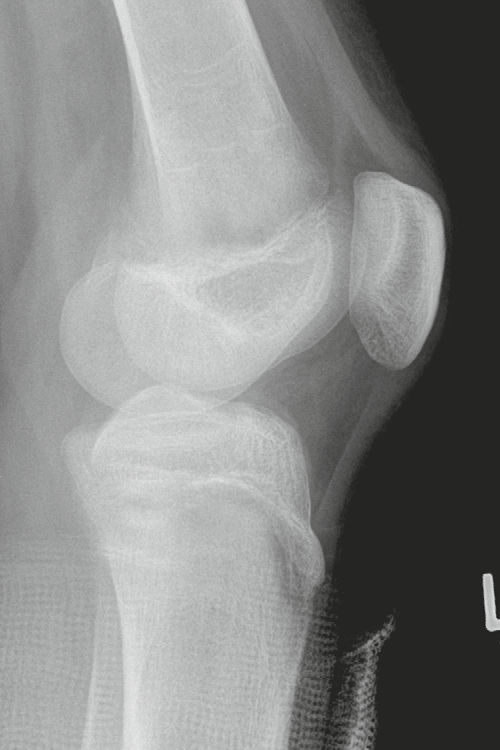

Typical radiographic appearance of JRA of the knee

* joint effusion * epiphyseal overgrowth * widening of the intercondylar notch * accelerated bone maturation